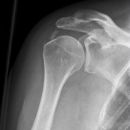

Schulter axial

Beurteilungskriterien